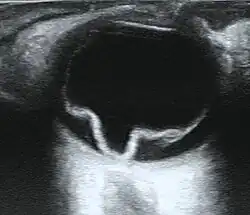

If the view of the retina is not clear, imaging techniques such as ultrawide-field fundus photography, B-scan ultrasonography, and optical coherence tomography (OCT) may help to identify a detachment.[8][13][14] Fundus photography provides a detailed view of the back of the eye, potentially revealing retinal tears or breaks.[8][16] On B-scan ultrasonography, a detached retina typically appears as a membrane floating in the vitreous cavity, moving in a wave-like motion.[19] OCT can detect fluid behind the retina, involvement of the macula (the central part of the retina), and other abnormalities within the retinal layers.[8][20]

MRI and CT scans are less commonly used for the diagnosis of retinal detachment, but they may be useful in certain cases.[8][10] In an emergency department setting, bedside ultrasonography can also be used for diagnosis.[8][13][14]